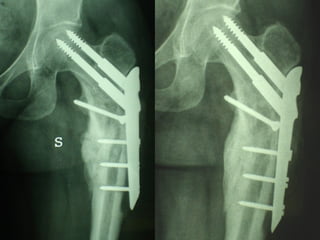

INDICAZIONI COMUNI Fratture sovracondiloidee Fratture intercondiliodee Fratture diafisarie distali PARTICOLARI Fratture con grave osteoporosi Fratture periprotesiche

VANTAGGI CHIRURGIA MININVASIVA Mini Open Inserimento della placca sottocutaneo per scivolamento Viti percutanee Preservazione dei tessuti molli Ridotto danno vascolare Rapida ripresa funzionale

F, 68 y

LISS  NCB

NCB

Conclusioni Riduzione  anatomica Minimo trauma chirurgico Corretto equilibrio fra elasticità e stabilità Precoce mobilizzazione